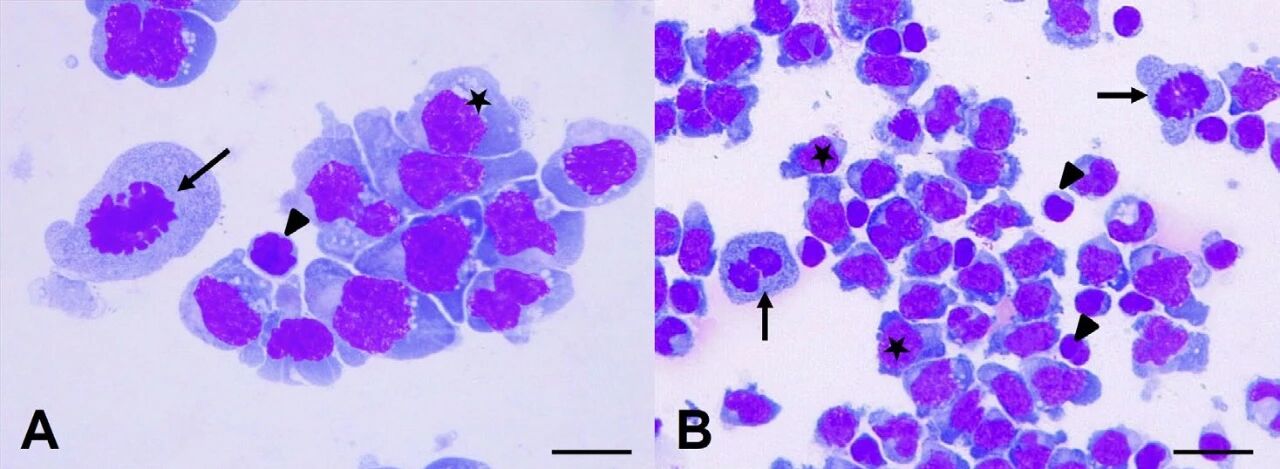

通过腰穿获得的脑脊液分析显示,淋巴细胞明显增多(837个/μL,蛋白14843.8mg/L),以中等和大型淋巴细胞为主,小型成熟淋巴细胞数量少(<20%),有罕见的有丝分裂象(下图)。这些发现提示为中等到大细胞淋巴瘤。

↑ 脑脊液显示出大圆细胞(星号),伴有少量中等嗜碱性、部分空泡化的细胞质。也可以看到有丝分裂像(箭头),以及小淋巴细胞(三角)。

免疫组化显示超过95%的细胞对CD3具有中等的膜和细胞质染色,而对PAX5的中等阳性细胞则不足3%,且呈核染色模式。因此,被认为最可能是T细胞来源,诊断为T细胞淋巴瘤。